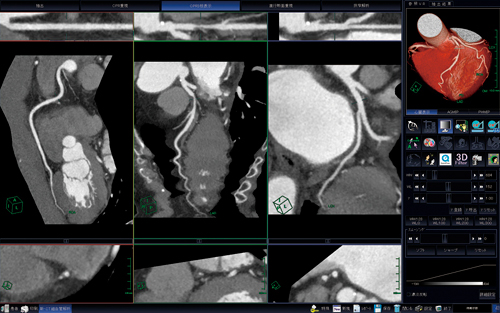

“新・CT細血管解析”は,冠動脈CTの解析ソフトウェアであり,冠動脈CT画像の読み込みと同時に左右冠動脈,大動脈,心臓(心筋)などに自動セグメンテーションされる(図1)。セグメンテーションされた各冠動脈に対して,中心線の修正と名前付けをすると,あとは画像をAngiographic ViewやCPR(図2),直交断面像,狭窄部解析(図3)などに切り替えてキャプチャするだけである。やはり偽陽性や偽陰性を作らないためにも,中心線の確認や狭窄部の評価を診療放射線技師がしっかりと行う必要があると考えればこそ,自動化による時間短縮はありがたい。さらに,このソフトウェアは,あらかじめ設定したDICOMタグを自動判別し,VirtualPlaceに転送された時点で前準備を行うAAA(Aze Auto Analyzer)が併用できることから,さらに処理時間の短縮が期待される。

図1 冠動脈の自動セグメンテーション

図2 CPR3枝表示

図3 冠動脈狭窄解析